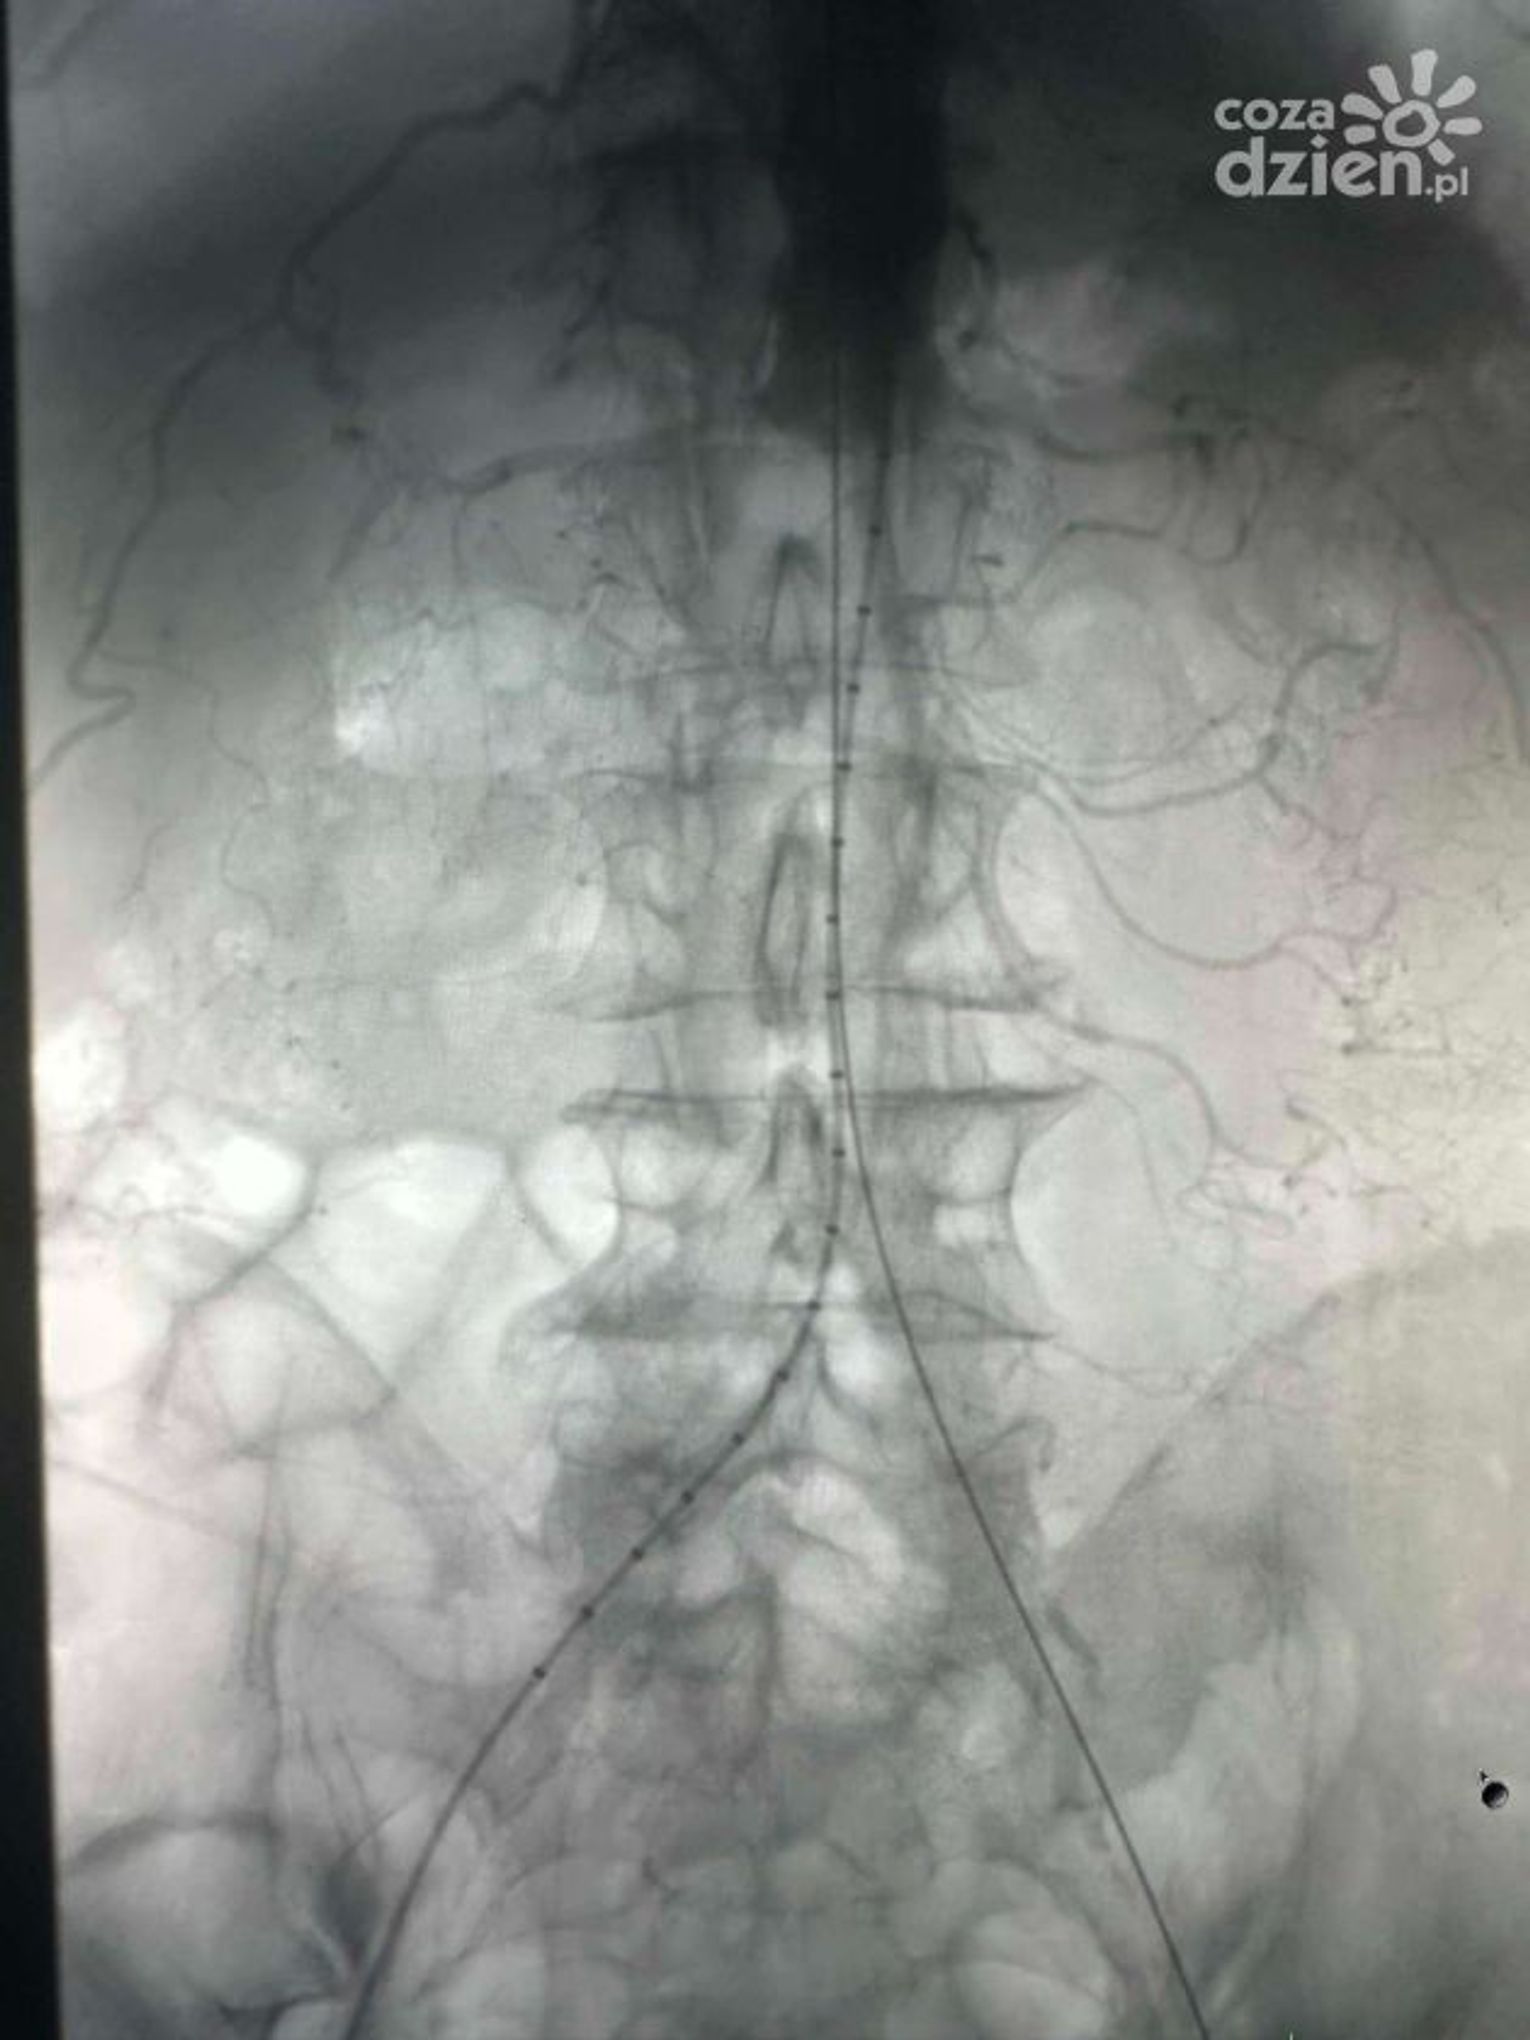

Takie operacje nie są codziennością, a wykonuje się je głównie w klinikach - i to dopiero od pięciu lat. W ostatnim czasie lekarze z Mazowieckiego Szpitala Specjalistycznego w Radomiu skutecznie udrożnili aortę podnerkową metodą wewnątrznaczyniową. - Pacjent mógł stracić nie tylko obie kończyny dolne, ale również i życie. Tutaj akurat wybraliśmy tę metodę, ponieważ ona była najbardziej adekwatna. Pacjent miał najwyższe szanse, żeby tę operację przeżyć i najwyższe szanse, żeby później po tej operacji przejść przez okres rekonwalescencji - tłumaczy lek. Renata Florek Szymańska, kierowniczka oddziału chirurgii naczyniowej w MSS.

Dzięki małoinwazyjnej metodzie wewnątrznaczyniowej nie jest konieczne otwieranie jamy brzusznej. - Było to nie tylko korzystniejsze dla zdrowia pacjenta, ale również i dla nas, chirurgów naczyniowych. Operacja trwała zdecydowanie krócej niż ta klasyczna. Polegała na wyłonieniu tętnic w pachwinach, co wiązało się też z mniejszymi ranami pooperacyjnymi - mówi Florek Szymańska.